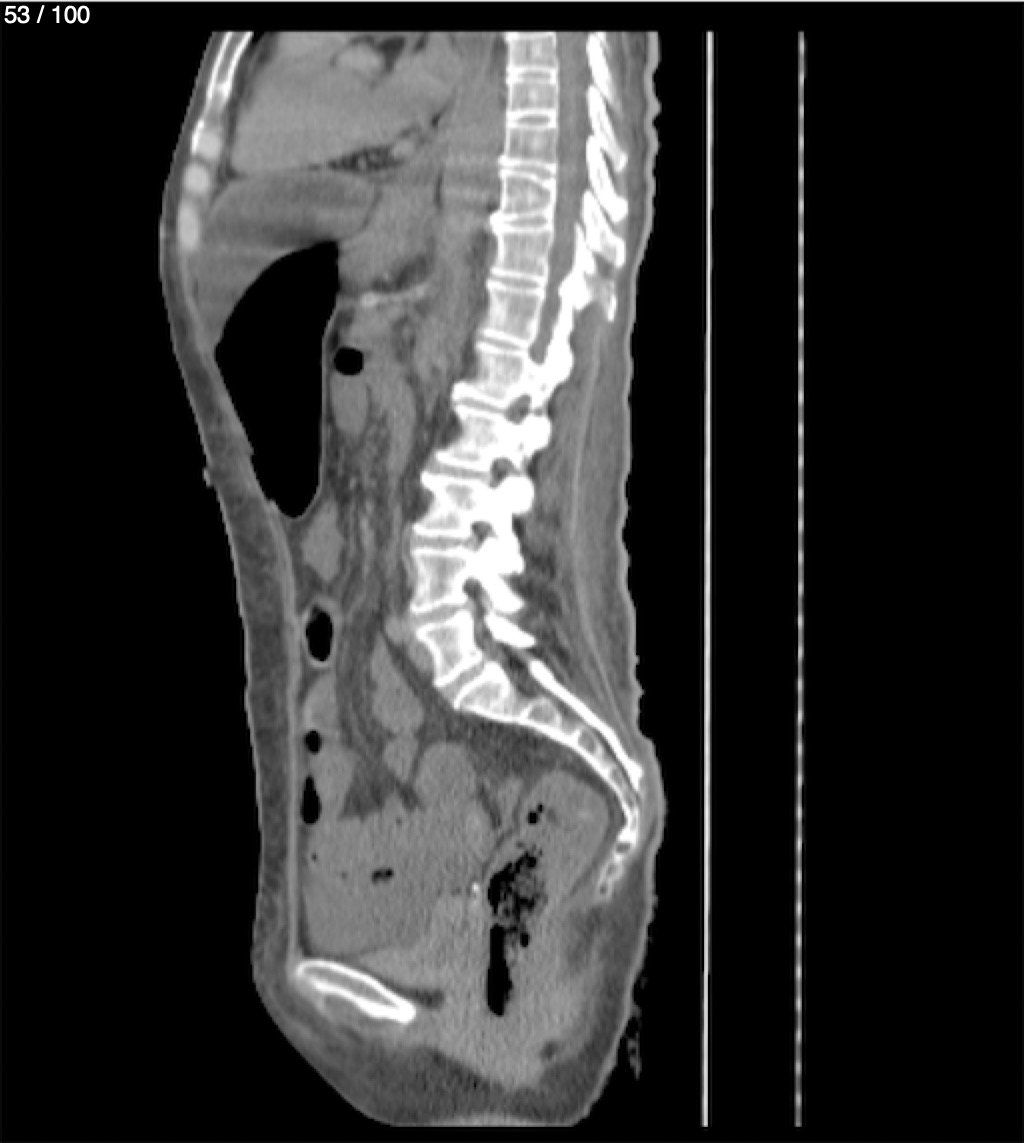

Hilda Geronimo Mendez 60A - T.C Abdomen Simple